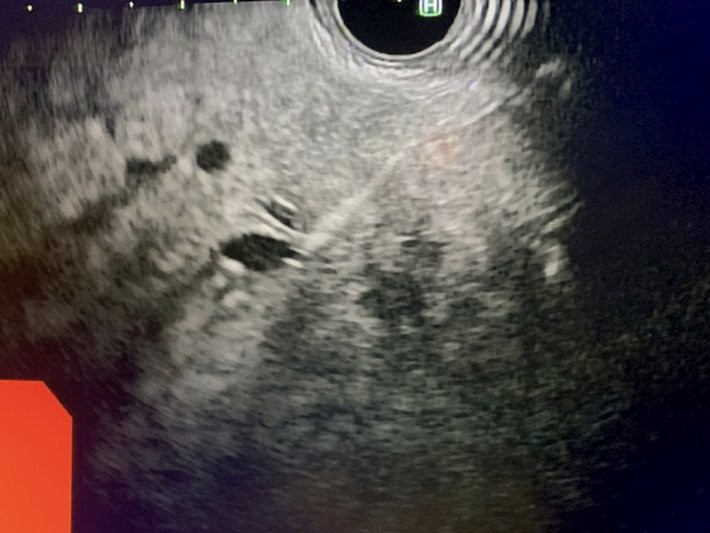

Under general anesthesia, esophagogastroduodenoscopy (EGD) was done using a gastroscope (Olympus America) and there were no esophageal or gastric varices noted. Next, EUS linear array echoendoscope (Olympus America) was passed into the esophagus and advanced into the stomach. The ultrasound image of the liver showed diffuse fatty infiltration. We performed portal pressure gradient using a 25-gauge Cook Echo Tip Insight needle (Cook Endoscopy, Winston Salem, NC). Pulse wave Doppler was used to confirm the middle hepatic vein. From the stomach through the left lobe of the liver, the middle hepatic vein was accessed, and three pressure measurements were taken using digital manometry (Figure 2). The average of 3 measurements from the middle hepatic vein was 17 mmHg. Pulse wave Doppler was used to confirm the left portal vein (Figure 3). Then from the stomach we measured the portal vein pressure by accessing the left portal vein and the average of three measurements was 18 mmHg (Figure 4), giving her a PPG of 1 mmHg. Using Doppler, we ensured there was no bleeding when the needle was withdrawn from both veins (Figure 5 and 6). After the portal pressure gradient measurement, liver core biopsies were done using a 19-gauge Boston Scientific FNB needle (Boston Scientific Marlborough, MA). From the stomach, the left liver lobe was biopsied with the use of EUS to confirm the absence of blood vessels in the needle’s trajectory. One pass and three actuations using the wet heparin technique was performed. The right liver lobe was biopsied from the duodenum and similar methodology was done using the same needle and technique. No bleeding was noted. Both core liver biopsies were sent in formalin to the pathology department for further evaluation.

Figure 3: Pulse wave Doppler of left portal vein prior to manometry.

Figure 6: Doppler of the left portal vein to ensure hemostasis post-manometry.